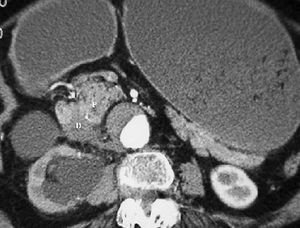

La forma más frecuente es la ausencia de rotación intestinal, que implica importantes alteraciones anatómicas valorables tanto en la ecografía como por la TC. Los principales hallazgos radiológicos son: alteración en la posición del duodeno, que no pasa entre la aorta y la arteria mesentérica superior (AMS); la localización en el hemiabdomen derecho de las asas de intestino delgado y en hemiabdomen izquierdo las de intestino grueso, y una verticalización o inversión de los vasos mesentéricos respecto a su posición normal, quedando la AMS a la derecha y la vena mesentérica superior (VMS) a la izquierda1,2 (fig. 1).

Fig. 1--Malrotación intestinal. (A) y (B) Tomografía computarizada con contraste oral e intevenoso mostrando inversión de la arteria mesentérica superior (AMS) (punta de flecha) y la vena mesentérica superior (flecha). La tercera porción duodenal (D) no cruza la línea media entre la aorta y la AMS, localizándose las asas de yeyuno a la derecha.